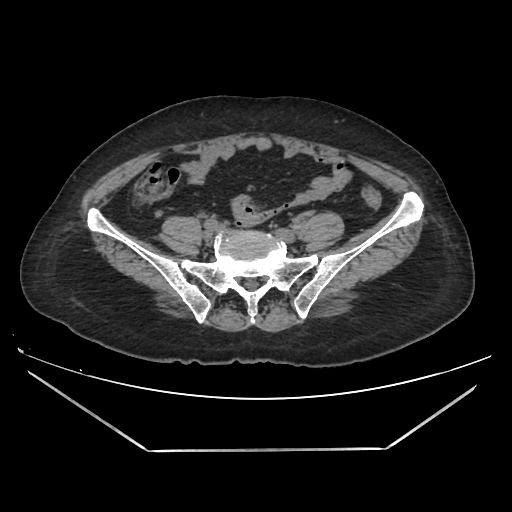

A CT abdomen revealed a left adrenal cortical tumor.

CT images: